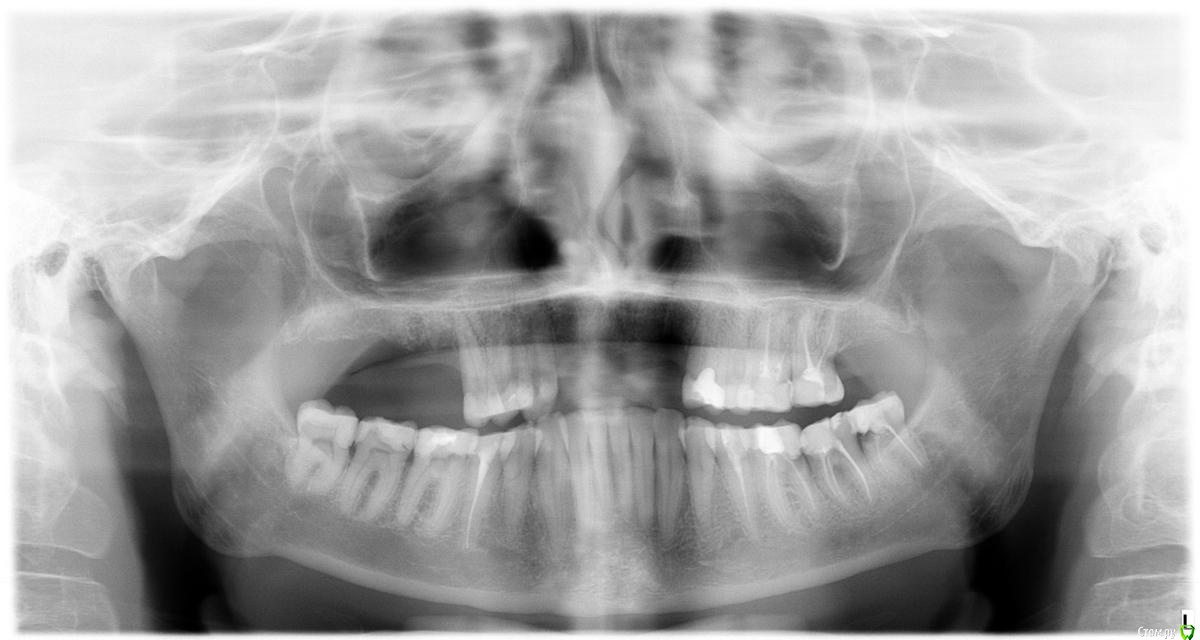

horoshie.veshi Опубликовано 7 августа, 2016 Поделиться Опубликовано 7 августа, 2016 (изменено) Добрый день. Имплантирую Нобель Реплейс:- фронт: клык - один имплант, резцы 1-3 - на два импланта мост- жевательные (верх): точно 6 и планировала 7. удаление (очень сложное) было в июне. на днях хирург посмотрел орто, сказал все ОК, можно имплантировать, но нужен синус (закрытый): материал bio-oss + мембрана bio-gide + применение мемб.техники + сам синус, итого сверху 70 тысяч, которые для меня неожиданны и очень накладны т.к. до этого дня врач убеждал, что заживление идет хорошо, и синус точно не понадобится. Теперь, скорее всего, вместо 7 придется делать с-л (из бюджета выпадаю). Прошу вашего мнения, действительно ли нужен закрытый синус лифтинг в моей ситуации? Полный размер: здесь. Спасибо! Изменено 7 августа, 2016 пользователем horoshie.veshi Ссылка на комментарий

rivezico Опубликовано 7 августа, 2016 Поделиться Опубликовано 7 августа, 2016 (изменено) Похоже на то, но для более точной информации нужен КТ. Часто в подобных случаях делают синус на сгустке или бикортикальную фиксацию. Изменено 7 августа, 2016 пользователем rivezico 1 Ссылка на комментарий

Bier Опубликовано 7 августа, 2016 Поделиться Опубликовано 7 августа, 2016 Согласен, нужно на КТ измерить кость, тут накладывается одно на другое, не очень видно. Ссылка на комментарий

horoshie.veshi Опубликовано 7 августа, 2016 Автор Поделиться Опубликовано 7 августа, 2016 (изменено) Спасибо, КТ делала до удаления 6-ки (7-ка удалена 4 года назад), по нему был вердикт, что с-л не нужен, кости в районе жевательных зубов хватает, и был сделан расчет стоимости лечения, и я внесла предоплату. "Необходимость" С-Л появилась буквально на днях, спустя 2 месяца после удаления 6-ки, до этого по снимкам он был не нужен, и этот момент меня очень смущает. Предлагала ему сделать КТ, но мне кажется, он уже принял окончательное решение, ему не нужно КТ, чтобы увидеть, что "кости все-таки мало" Изменено 7 августа, 2016 пользователем horoshie.veshi Ссылка на комментарий

Bier Опубликовано 7 августа, 2016 Поделиться Опубликовано 7 августа, 2016 после удаления всегда происходит атрофия так что старое КТ тут не поможет. Мне для принятия решения в этом случае нужна КТ, если вам интересен ответ врачей форума, надо сделать. А переубеждать своего врача дело неблагодарное. 3 Ссылка на комментарий

Bier Опубликовано 11 августа, 2016 Поделиться Опубликовано 11 августа, 2016 Здравствуйте, спасибо за снимок. Там примерно 8,5-9мм костной ткани до синуса. Можно установить имплантаты такого размера вообще без синуслифтинга, можно сделать закрытый синуслифтинг (в данном случае костные материалы и мембраны можно не использовать) и поставить стандартные 10мм имплантаты. Обратите внимание своего стоматолога на верхние моляры слева. (6й и 7й зубы) 1 Ссылка на комментарий